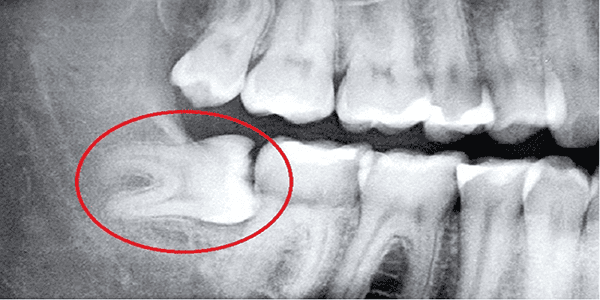

Răng khôn, hay còn gọi là răng số 8, là chiếc răng mọc cuối cùng trên cung hàm và thường xuất hiện ở độ tuổi trưởng thành (17-25 tuổi). Tuy nhiên, không phải ai cũng may mắn có răng khôn mọc thẳng và đúng vị trí. Tình trạng răng khôn mọc lệch, mọc ngầm không[…]

Răng khôn (hay răng số 8) là những chiếc răng mọc cuối cùng trên cung hàm, thường xuất hiện ở độ tuổi từ 17 đến 25. Hầu hết mọi người đều cảm thấy lo lắng khi nhắc đến chiếc răng này và băn khoăn “Có nên nhổ răng khôn không?”. Theo các chuyên gia nha[…]